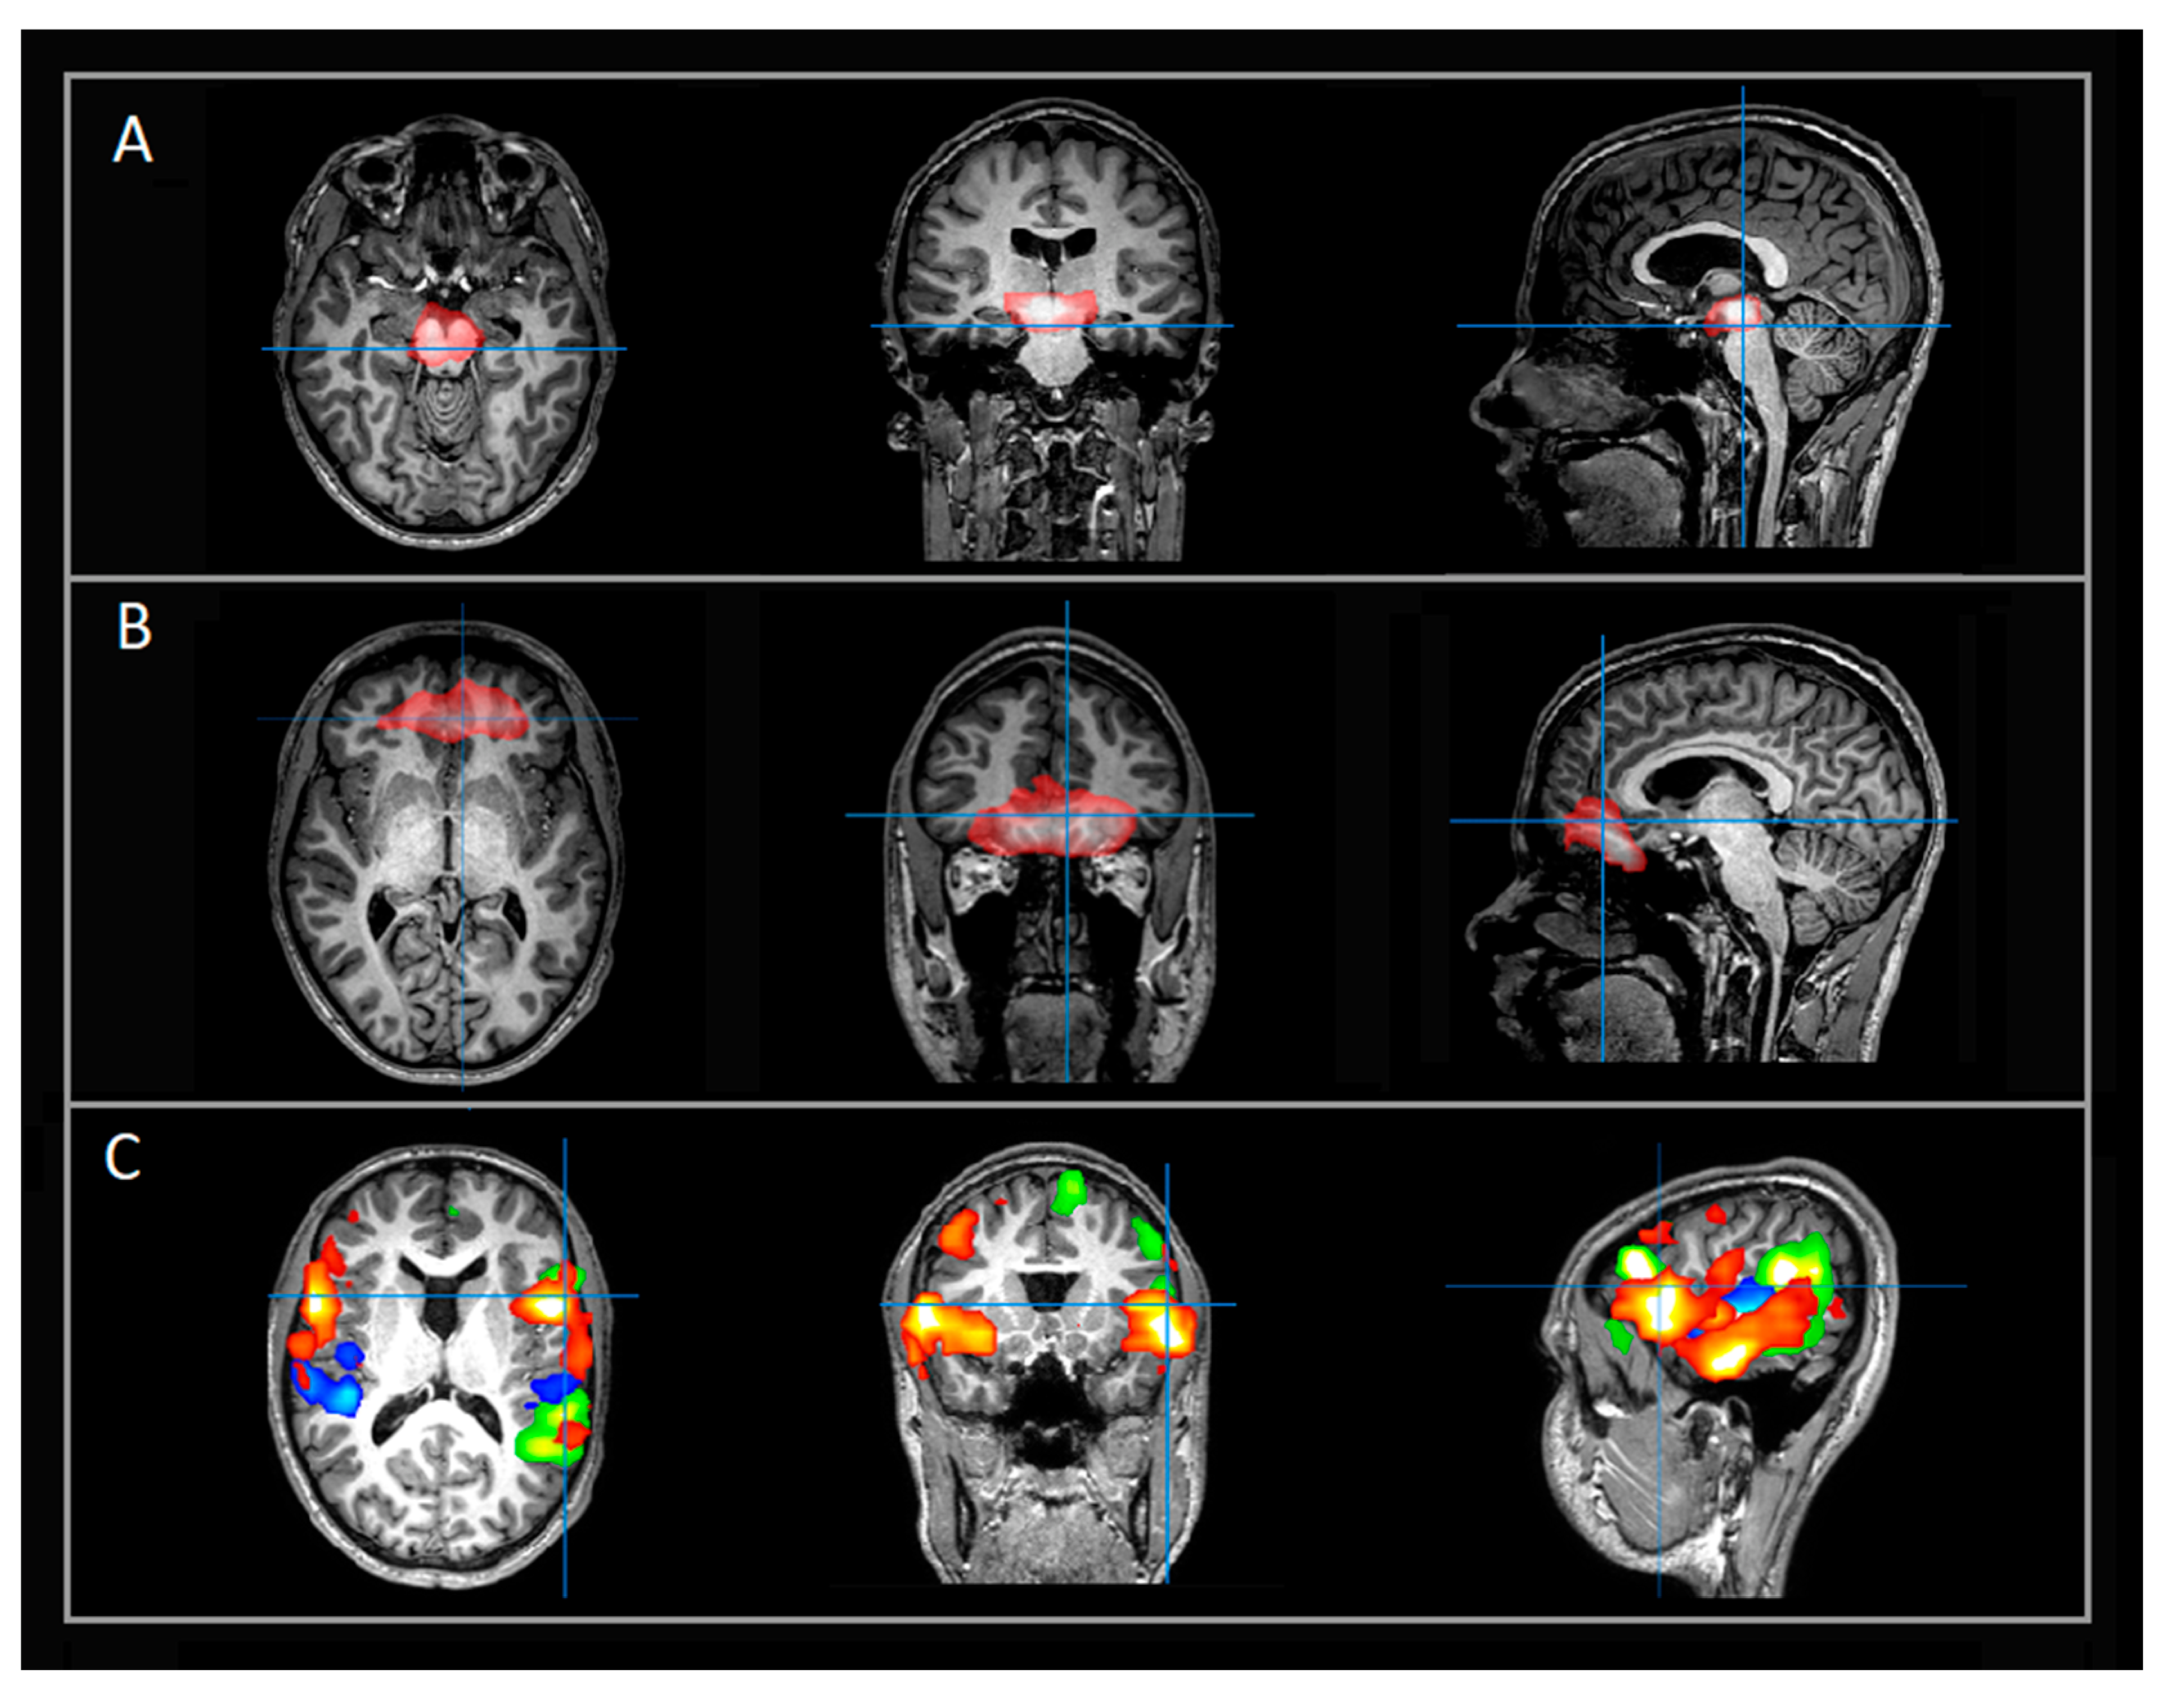

Her rs-fMRI revealed aberrant and strongly deactivated networks localized to the brainstem and other subcortical structures involved in monoamine synthesis (Figure 1A). Additional aberrant networks extended over multiple bilateral regions including the ventromedial prefrontal cortex (vmPFC), the left fronto-temporo-parietal, and occipital networks with deactivation patterns localized to language and cognition-related regions (Figure 1B). Despite her deficits, she had typical frontoparietal (FP), language, and motor RSNs (Figure 1C). Suspicion for neurotransmitter deficiency was triggered given her history of prior severe late regression without known brain insult in the presence of aberrant deactivation patterns between the brain stem and vmPFC with a similar spatial distribution as the monoaminergic networks. Examples of typical rs-fMRI networks localized to the subcortical and brainstem networks (Figure 2A), vmPFC (Figure 2B), and language networks (Figure 2C) are provided for a case-control.

Figure 1. Select rs-fMRI networks in 16-year-old patient with ASD (case study). All images are in radiological orientation. The indicated networks are overlaid on T1-weighted images in axial, coronal, and sagittal views. (A) Evidence of atypical and strongly deactivated subcortical and brainstem networks in similar anatomic spatial distribution as the monoaminergic networks; (B) Additional atypical networks extending over multiple bilateral regions including vmPFC, FP, temporal, and occipital regions; (C) Normal language networks with bilateral presence of typical connectivity between receptive and expressive regions. Row A, blue color denotes BOLD deactivation, red color denotes BOLD activation. Rows B and C, each color denotes a separate network. Abbreviations: rs-fMRI = resting state functional magnetic imaging; vmPFC = ventromedial prefrontal cortex; FP = fronto-parietal.

Figure 2. Select rs-fMRI networks in patient (case–control) evaluated for possible seizure focus (not detected, otherwise typical networks). All images are in radiological orientation. The indicated networks are overlaid on T1-weighted images in axial, coronal, and sagittal views. (A) Example of typical subcortical and brainstem networks; (B) Additional examples of typical networks extending over bilateral vmPFC region; (C) Typical language networks. Rows A and B, red color denotes BOLD activation. Row C, each color denotes a separate language network. Abbreviations: rs-fMRI = resting state functional magnetic imaging; vmPFC = ventromedial prefrontal cortex.